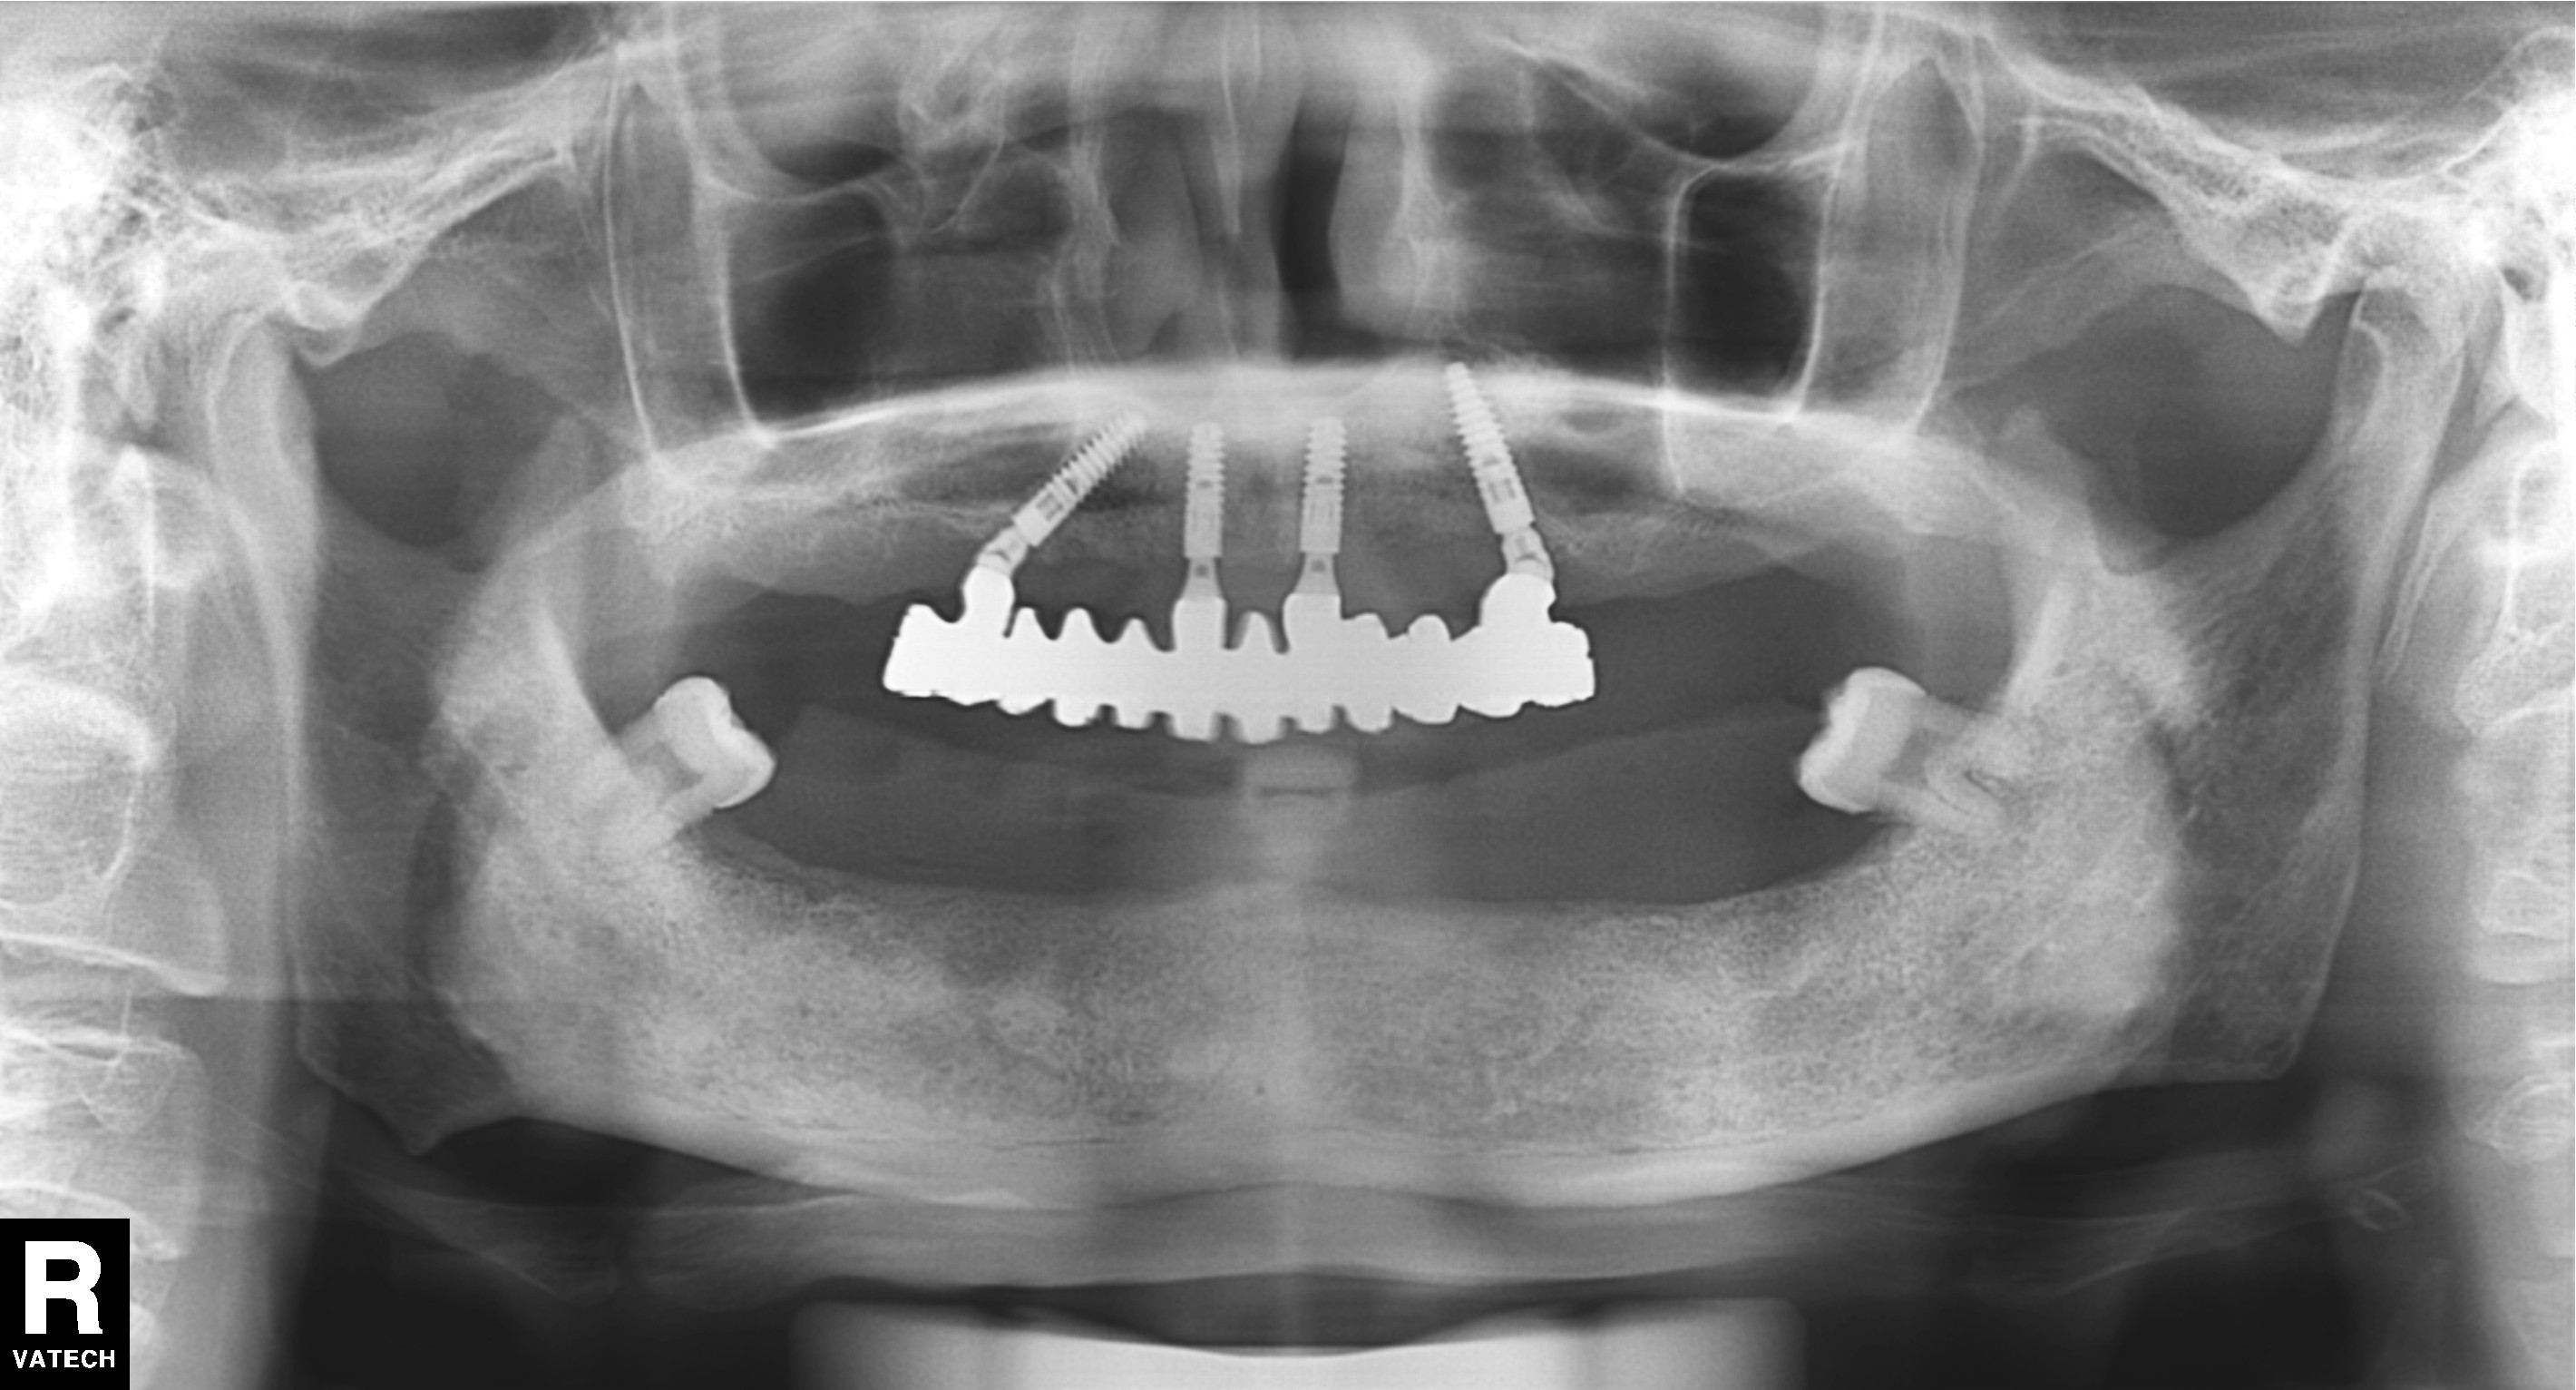

上頜做完4顆種植牙後拍片檢查

目前種植牙全口做的話,通常是采用上下各種植6-8顆牙齒,也就是說上下一共做種植牙12-16顆,具體(ti) 多少顆醫生會(hui) 根據牙槽骨的情況來定的,大家基本上不用擔心這個(ge) 問題。

這通常隻是單純的全口種植牙的價(jia) 格(包含了牙根和上部修複),但是一般不包含植骨需要的骨粉骨膜、牙周治療以及拔牙、檢查拍片等費用,所以在10幾萬(wan) 的基礎價(jia) 格上,可能還會(hui) 增加數千左右的費用支付其他的費用。